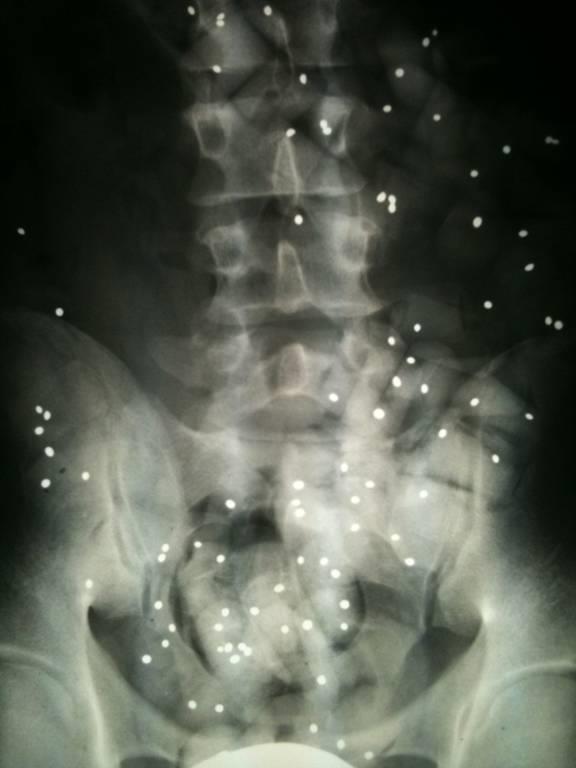

- erst einmal sind keine Röntgenbilder erforderlich